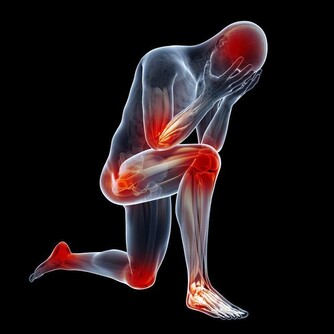

跌倒不但會造成腦部受傷、骨折等嚴重外傷,還會引發“跌倒恐懼症”,給老人帶來極大的心理創傷。

1.跌倒造成身體器質性傷害

跌倒損傷最嚴重的是髖部骨折,成為老年人首位傷害死因。

另外會造成顱腦損傷,可直接導致死亡。

2.跌倒讓身體功能減退

俗話說,傷筋動骨100天。老年人跌倒後通常卧床,或者傷殘肢體制動很長一段時間,

會因為廢用等因素導致肌肉萎縮、骨質疏鬆;

最嚴重的可造成關節攣縮,將嚴重影響肢體功能,降低恢復後老人的活動能力,甚至過早死亡。